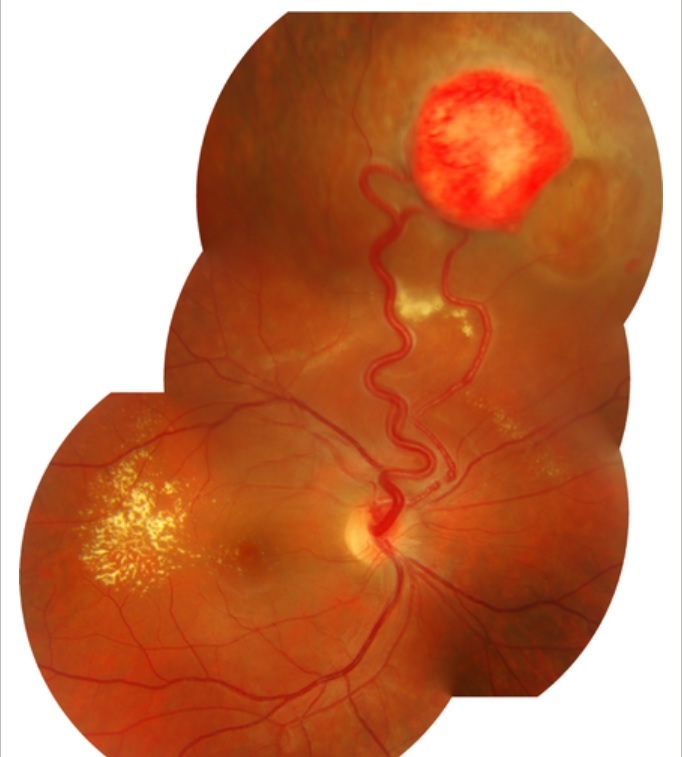

Descreva o hemangioblastoma ou hemangioma capilar?

Tumor avermelhado e arredondado formado por células angioblásticas e capilares hiperplásicos.

Qual é a porcentagem dos pacientes com Doença de Von-Hipple-Lindau que apresentam Hemangioma Capilar de Retina?

45-65%

Qual é a porcentagem de bilateralidade dos Hemangioblastomas nos pacientes com Doença de Von-Hipple-Lindau?

50%

Qual é a porcentagem dos pacientes com Doença de Von-Hipple-Lindau que apresentam Hemangioma Capilar de Retina peripapilar?

25%

Quais são as principais complicações dos Hemangioblastomas?

Exsudação

DR Seroso

Hemorragia Vítrea